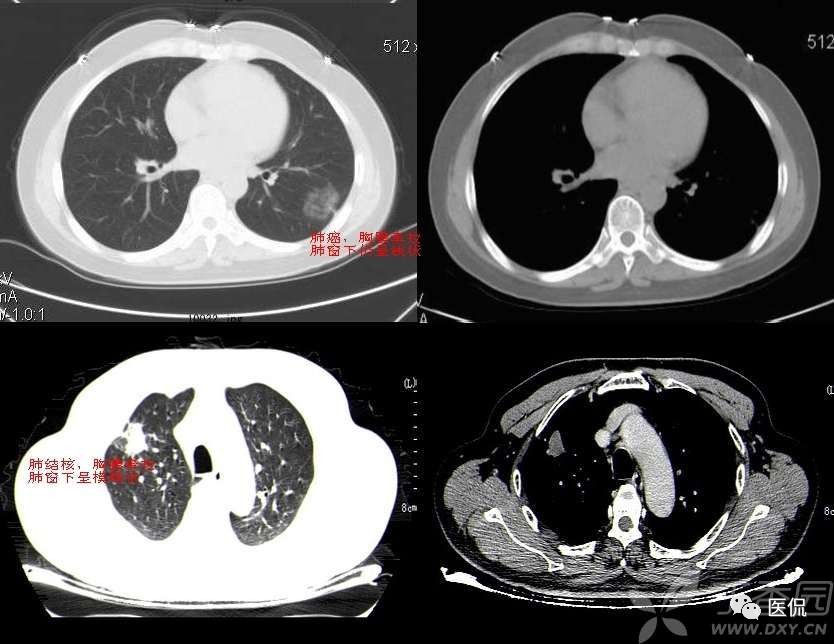

血管集束征

血管集束征在影像上表现为肺结节周围一支或几支血管到达瘤体内或在瘤体边缘截断或穿过瘤体的现象。其形成包括以下三种情况:

(1)肺血管进入肿瘤内或穿过肿瘤;

(2)肺血管受牵拉向病灶移位;

(3)肺血管到达肿瘤的边缘截断。

血管集束征的形成是由于肿瘤组织向血管支气管鞘或小叶间隔生长,瘤体内纤维组织增生或瘢痕形成,牵拉临近血管向瘤体集中所致。其中进肺门侧的血管束、支气管构成,血管壁多为扩张的小动脉,说明肺癌供血丰富;远肺门侧的血管束由扩张的小静脉组成,可能和静脉回流受阻有关。血管集束征的形成机制是由于恶性肿瘤细胞产生肿瘤生成因子诱发肿瘤形成新生血管,尤其是血供丰富的恶性肿瘤,由于其生长活跃,常致使肿瘤供血的血管代偿性增粗,这些血管长扩张或伴有肿瘤细胞的支气管动脉鞘浸润或瘤栓形成。这就意味着,肿瘤或结节周围血管是否增粗表明该病变的良恶性程度。血管集束征的出现与肿瘤或结节的大小有关,小于1公分的病灶较少出现;腺癌出现的的几率较高,因为腺癌供血丰富,纤维化形成的更明显。尤其要注意的是,一支血管引向结节或肿瘤内,不只仅见于恶性结节,也可见于良性病变如结核球、炎性假瘤或错构瘤。对于引向两性结节的这支血管可看作血管连接,而不是血管集束征。多支血管引向病变即出现了血管集束征这在恶性肿瘤出现的机会较高。此外,肺恶性结节累计静脉的机会更多,病灶不论大小,如果见到结节累及静脉,强烈提示恶性可能。判断某支血管是动脉还是静脉,主要根据其走形来判断,动脉主要和支气管伴行,静脉主要位于病灶的边缘绕行。关于血管集束征的血管,有学者认为大多数并非肿瘤供血血管或肿瘤血管,被肺癌卷入的肺动脉不参与肿瘤供血。另外,肺癌瘢痕的形成和癌巢的增殖与破坏与血管集束征和胸膜凹陷征的形成有关。血管集束征主要见于肺癌,尤其是腺癌和肺泡细胞癌。但是该征像不仅见于恶性肺结节,肺良性病变如结核球、球形肺炎等也可见到。所以仅根据血管集束征判断病变的良恶性并不是完全可靠的。

腺癌粗大的引流血管: